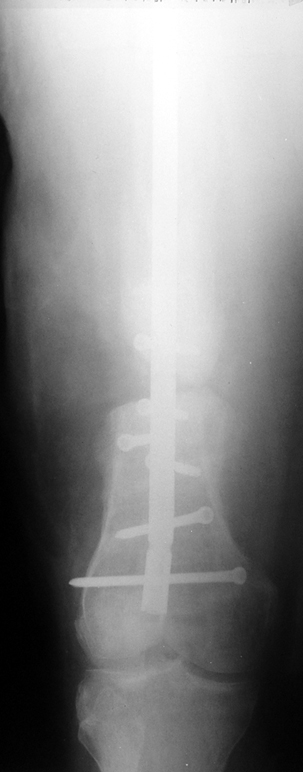

The duration of external fixation (external fixation index) depends on the amount of distraction required, and the extremity is prone to complications during this period. After the distraction phase is completed, the external fixator remains in place during the consolidation phase, which lasts twice as long as the distraction phase; but this period is hardly tolerated. If the external fixator is removed before sufficient consolidation is achieved, fractures, deformity and shortness will be the result. In our department, ‘lenghthening over nail’ method is used in order to decrease the external fixation index and increase patient comfort and activity level. In this method, the intramedullary nail is statically locked after the completion of the distraction phase, and external fixator is removed. The extremity is stabilized by the intramedullary nail during consolidation phase. In this way, complications due to long external fixation index or early removal of the external fixator are avoided.

Case 1